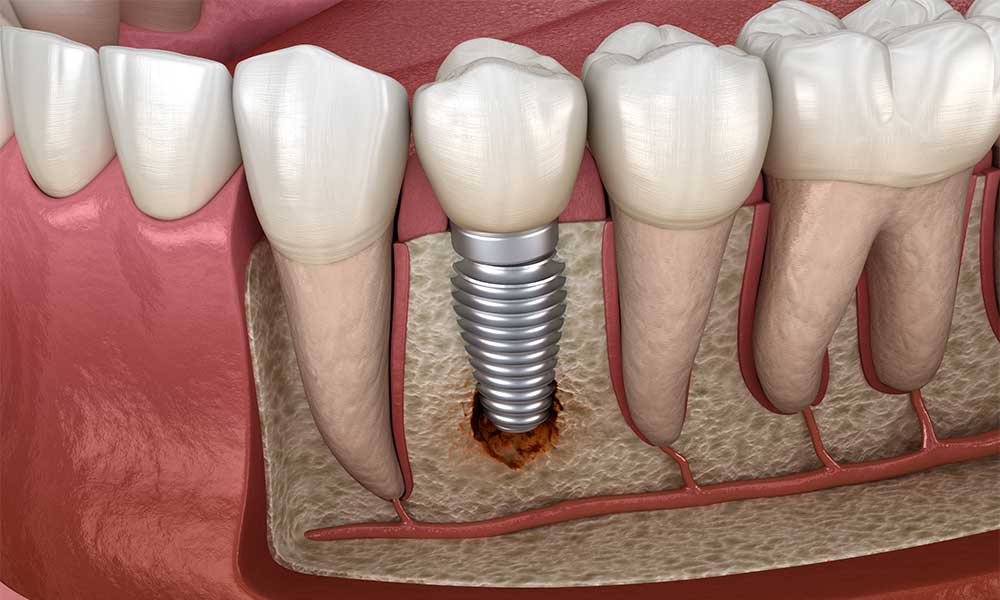

According to a study, infection and inflammation are among dental implants’ most common side effects. These are known as “peri-implants,” and they result from bacteria building up around the implant. Bacteria buildup may happen due to poor oral hygiene, improper implant placement and other pre-existing issues such as diabetes and gum disease. Also smoking and putting excessive force on the implants can also contribute to this problem. Treatment for infection may include antibiotics or deep cleaning. Surgical intervention may be required to remove the infected area and regenerate the bone if the condition is severe. Take a look at dental implant infection pictures below:

According to a research, peri-implantitis can take around 5 years to progress and result in symptoms. If you notice any of these dental implant infection signs after getting a dental implant, you should promptly contact your medical professional without waiting.